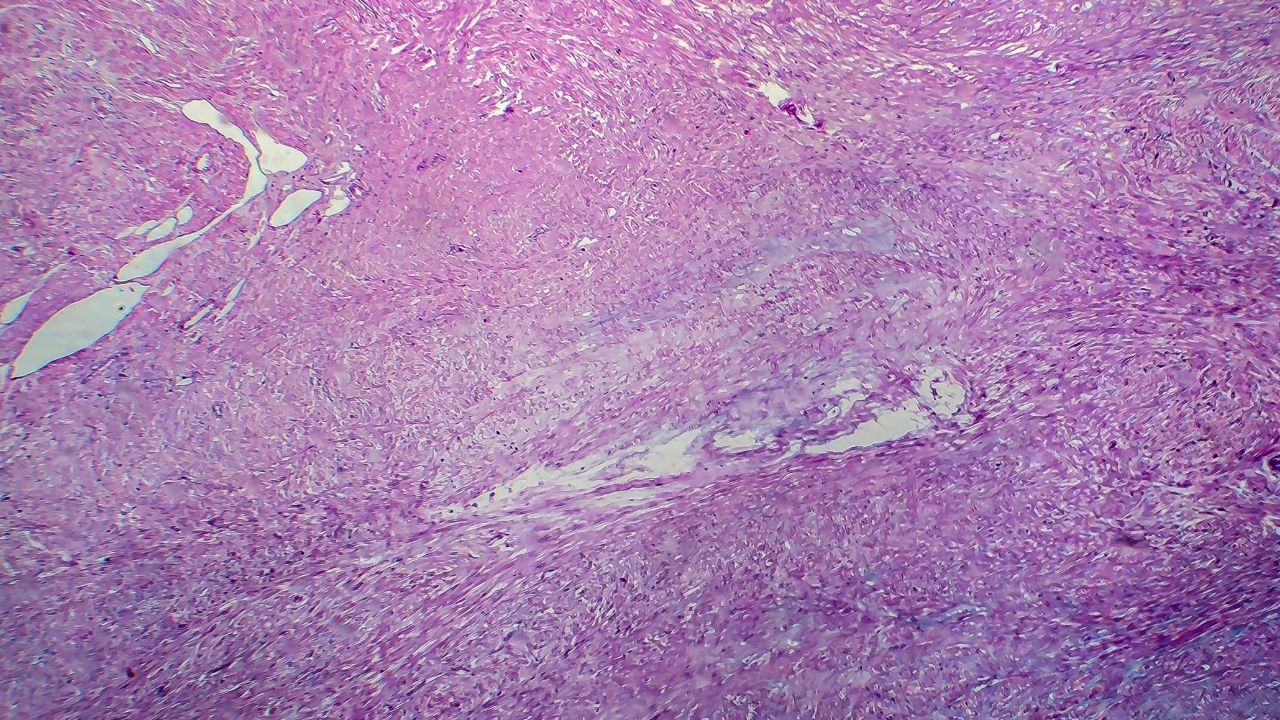

Kanserin erken evrede teşhisi, kanser tedavisinin başarısını önemli ölçüde arttırır. Kanserin erken teşhisi için kişinin bir şikayeti olmasa dahi rahim ağzı, meme, kalın bağırsak ve prostat kanserleri için kanser tarama testleri